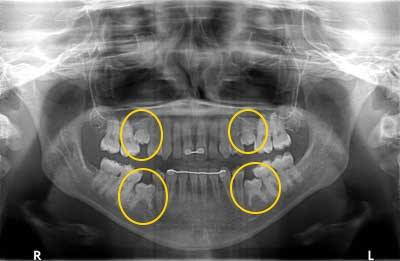

Reinkluzja rozpoznawana jest na podstawie badania stomatologicznego potwierdzonego badaniem radiologicznym.

Klinicznie obserwuje się infrapozycję zęba reinkludowanego – obniżenie powierzchni żującej zęba w stosunku do powierzchni zgryzu (skutek miejscowego zahamowania wzrostu kości wyrostka zębodołowego). Stwierdza się (nie w każdym przypadku) metaliczny odgłos opukowy lub utratę mobilności zęba przyczynowego.

Ostateczna diagnoza powinna być potwierdzona badaniem radiologicznym, umożliwiającym zróżnicowanie zęba reinkludowanego z zębem częściowo zatrzymanym oraz potwierdzającym obecność odpowiednika zęba stałego.